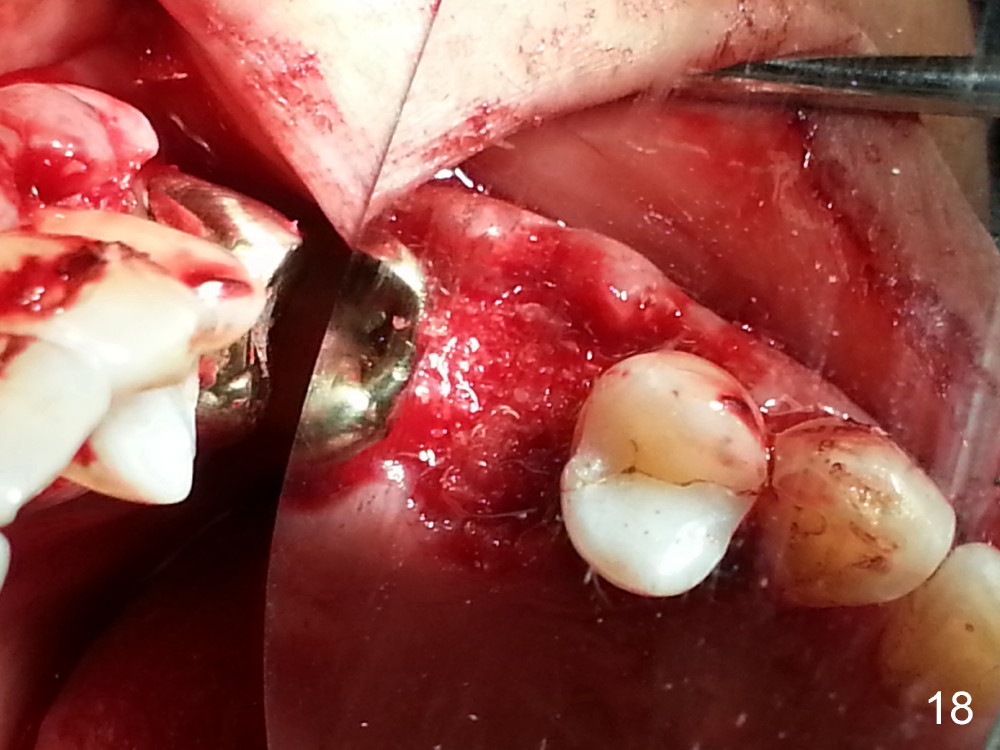

The tooth #13 appears to be affected by periodontits and occlusal trauma (Fig.1*). After using a periotome (Fig.2), the tooth is extracted (Fig.3). The buccal flap is raised (Fig.4). Gingival graft is to be harvested from the site of #15 (Fig.5). The tissue is elevated buccally (Fig.6) and separated (Fig.7). The donor site is covered by a collagen membrane (Fig.8*). A diamond bur is used to induce bleeding from the socket (Fig.9*). Osteotomy is initiated (Fig.10) and enlarged (Fig.11,12). A tapered implant is being placed (Fig.13-15) following internal sinus lift (Fig.16,17). The implant is placed subcrestally, followed by bone graft (Fig.18), soft tissue graft (Fig.19), and suturing (Fig.20 <, Fig.21).